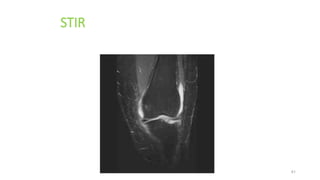

1-STIR (short TI inversion recovery)

•• STIR

•• is an (IR)pulse sequence that uses a TI that

corresponds to the time it takes fat to recover from

full inversion to the transverse plane so that there is

no longitudinal magnetization corresponding to fat.

STIR

•• When the 90° excitation pulse is applied, the fat

vector is flipped through 90° to 180° and into full

saturation.

•• so that the signal from fat is nulled.

•• STIR is used to achieve suppression of the fat signal

in a T1 weighted image.

•• Generally, a TI value of around 100-200 ms is used.

• • Uses

• • Used to suppress the fat signal in T1 weighted

• image.

• • Disadvantage

• • Should not be used with contrast enhancement.

• • Parameters

• • TE = 10-30 ms

• • TR = 2000 ms

• • TI = 150-200 ms

• • Average scan time = 5-15 minutes.